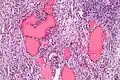

Low magnification -

Higher magnification